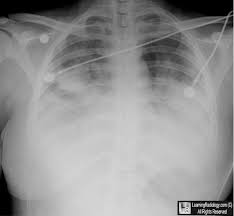

What is Fat Embolism?The term 'fat embolism' was mentioned in the season finale of the popular TV series House. “Yeah, she died from a fat embolism, riding in the ambulance ... read more

Bone marrow escaped into his bloodstream, causing a fat embolism, similar to a blood clot, to form in his lungs. “He almost died again, and he stayed in the ... read more